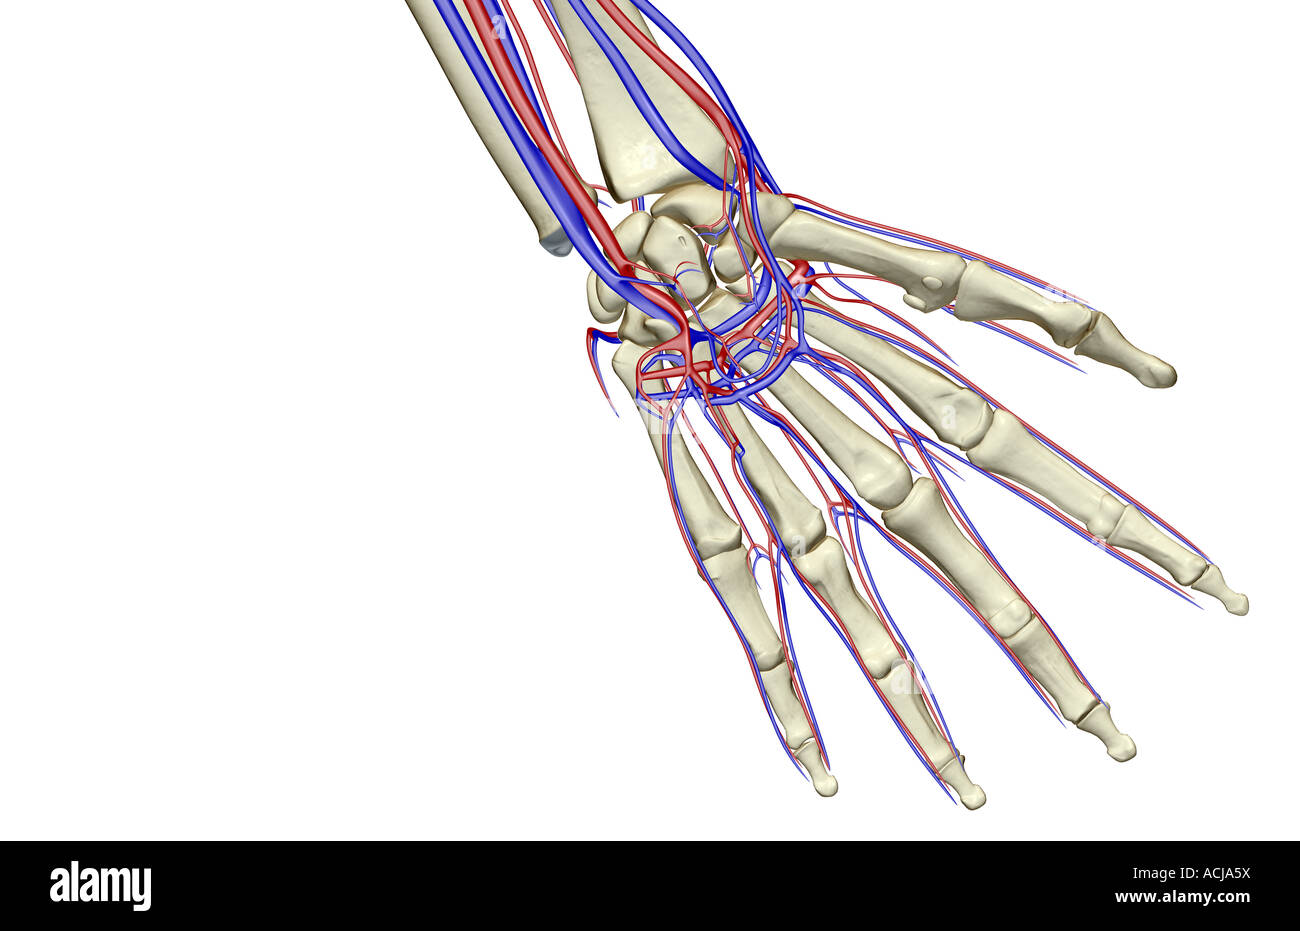

The blood supply of the hand Stock Photohttps://www.alamy.com/image-license-details/?v=1https://www.alamy.com/stock-photo-the-blood-supply-of-the-hand-13168357.html

The blood supply of the hand Stock Photohttps://www.alamy.com/image-license-details/?v=1https://www.alamy.com/stock-photo-the-blood-supply-of-the-hand-13168357.htmlRFACJA5X–The blood supply of the hand